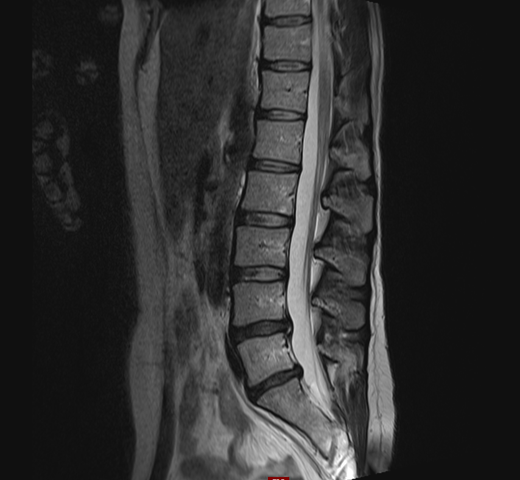

Im Vordergrund steht die schmerzlindernde Behandlung der Beschwerden damit man so aktiv wie möglich bleiben kann. Ein Bandscheibenvorfall kann unbemerkt bleiben aber auch zu. Die Genesung lässt sich durch die Schmerztherapie zwar nicht beschleunigen. Erstes Mittel der Wahl ist die konservative Therapie. Bis dahin können verschiedene schmerzlindernde Behandlungen helfen mit den Beschwerden zurechtzukommen. Andernfalls erfolgt eine direkte Überweisung an einen Orthopäden. Wie ein Bandscheibenvorfall behandelt. Durch Druck- und Fehlbelastungen des vorderen Bandscheibenanteils tritt Bandscheibenmaterial in der LWS normalerweise nach hinten oder hinten seitlich aus. Wie wird ein Bandscheibenvorfall behandelt.

Bandscheibenvorfälle werden nicht immer operiert. Was ist ein Bandscheibenvorfall. Andernfalls erfolgt eine direkte Überweisung an einen Orthopäden. Durch Druck- und Fehlbelastungen des vorderen Bandscheibenanteils tritt Bandscheibenmaterial in der LWS normalerweise nach hinten oder hinten seitlich aus. Dabei wird die Bandscheibe entfernt und ein Platzhalter entweder eine Bandscheibenprothese oder ein Cage Titan- oder Kunststoffring eingesetzt. Wie wird ein Bandscheibenvorfall behandelt. Bandscheibenvorfälle werden nicht immer operiert.